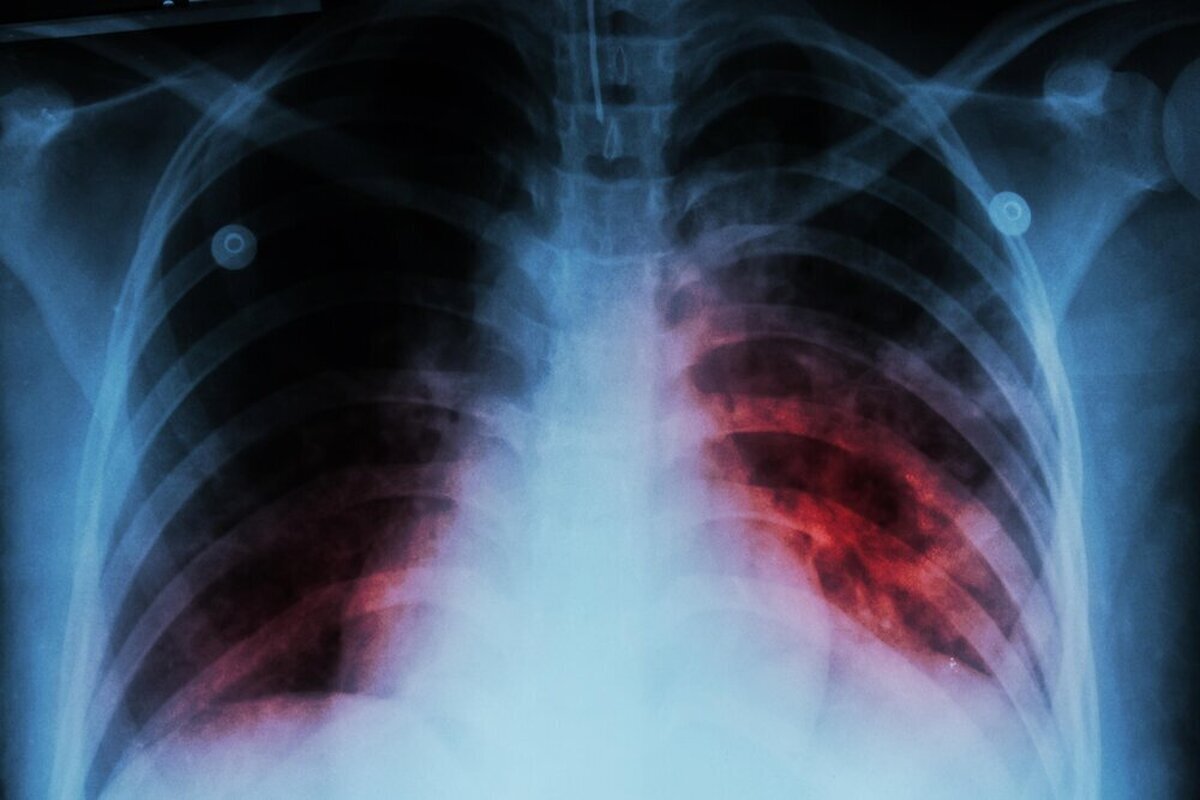

به گزارش مجله خبری نگار/برنا، قباد مرادی در حاشیه همایش گرامیداشت روز ملی سل که امروز دوشنبه، ۲۱ مهرماه در وزارت بهداشت برگزار شد اظهار داشت: برآورد سازمان جهانی بهداشت از میزان بروز سل در کشور حدود ۱۱ مورد به ازای هر ۱۰۰ هزار نفر جمعیت است.

وی افزود: بر اساس دادههای ثبتشده، میزان کشف موارد سل در کشور بین ۷ تا ۸ در هر ۱۰۰ هزار نفر است. هنوز پاسخ قطعی به این پرسش که آیا برآورد سازمان جهانی بهداشت دقیقتر است یا میزان شناسایی ما کمتر از واقعیت است، مشخص نشده و در حال بررسی هستیم تا به پاسخ علمی و قطعی برسیم.

دکتر مرادی با اشاره به وضعیت کنترل بیماری سل در ایران، گفت: حتی اگر همان برآورد ۱۱ در ۱۰۰ هزار نفر را ملاک قرار دهیم، در مقایسه با کشورهای همسایه، ایران یکی از بهترین عملکردها را در زمینه کنترل بیماری سل دارد. تنها یکی دو کشور از حاشیه خلیج فارس با جمعیت کمتر در این زمینه شرایط بهتری دارند که طبیعتاً کنترل بیماری در جمعیتهای محدود سادهتر است.

رییس مرکز مدیریت بیماریهای واگیر افزود: در شرق کشور، دو کشور همسایه با یکی از بالاترین میزان بروز سل در جهان قرار دارند و یکی از آنها تخمینی بیش از ۲۰۰ مورد به ازای هر ۱۰۰ هزار نفر جمعیت دارد. با توجه به وجود حدود ۵ میلیون نفر مهاجر از این کشورها در ایران، حفظ این سطح از کنترل بیماری، دستاوردی بسیار ارزشمند برای نظام سلامت محسوب میشود.